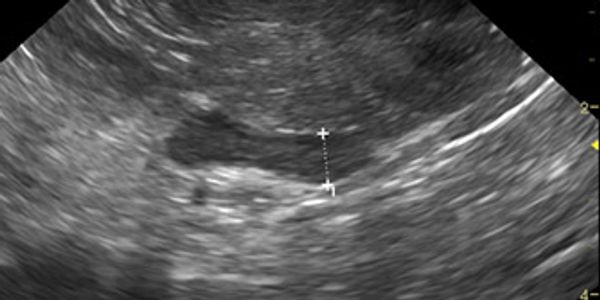

The advanced diagnostic technique of ultrasound has become a standard of care in veterinary medicine allowing the practitioner the opportunity to opt for less invasive testing. The speed and accuracy of results frequently outweigh the client & patient stress, expense, and pain of more invasive diagnostics and surgery. When combined with various minimally-invasive biopsy techniques, a diagnosis can be safely and accurately determined in most cases. Conversely when based on ultrasound findings, the practitioner can be confident that more aggressive (and often necessary) procedures such as exploratory laparotomy are definitively indicated to further characterize or resolve a given problem.